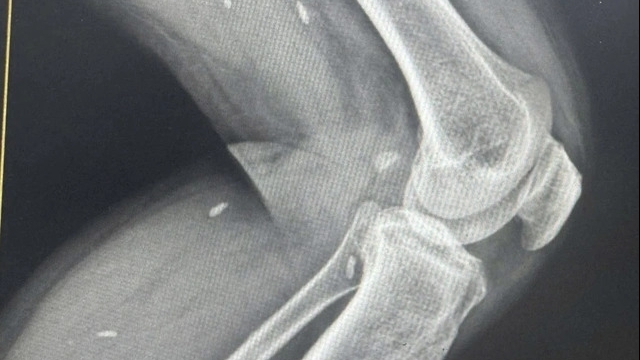

Bệnh nhân là thiếu niên 13 tuổi, trú tại xã Vĩnh Tuy, tỉnh Tuyên Quang, nhập viện trong tình trạng bỏng và chấn thương vùng tay, chân và mặt. Theo thông tin từ gia đình, tai nạn xảy ra khi bệnh nhi vừa sạc pin vừa sử dụng điện thoại. Thiết bị bất ngờ phát nổ, gây tổn thương phần mềm và tiềm ẩn nguy cơ để lại di chứng, ảnh hưởng lâu dài đến sức khỏe và sinh hoạt.

| Bệnh nhân nhập viện trong tình trạng bỏng và chấn thương vùng mặt, tay, chân do điện thoại phát nổ khi vừa sạc vừa sử dụng |